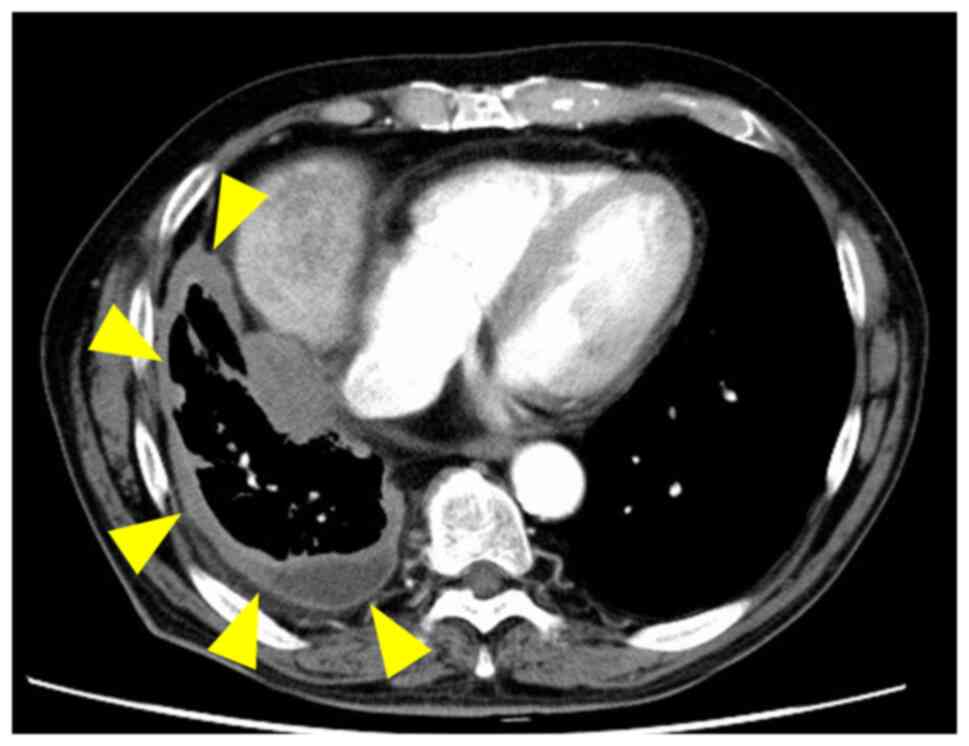

The patient was a 73-year-old male who visited the National Cancer Center Hospital (Tokyo, Japan) with a major symptom of progressive dyspnea. The patient had been exposed to asbestos from the age of 25 to 60 years. Enhanced CT detected pleural thickening and pleural effusion on the right side (Fig. 1A). Pathological diagnosis using pleural biopsy suggested DMM. Pleurectomy/decortication was performed and the definitive diagnosis from surgically resected tumor tissues was DMM (pT2 pN1 cM0 pStage II). The tumor tissue obtained at the time of surgery was used to establish the cell line. After seven months, multiple liver metastases occurred and the patient developed jaundice and died from pneumonia and respiratory failure due to DMM recurrence.